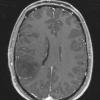

NEOPLASMS (GLIAL)

Astrocytoma, IDH-mutant, WHO Grade 2 (10)